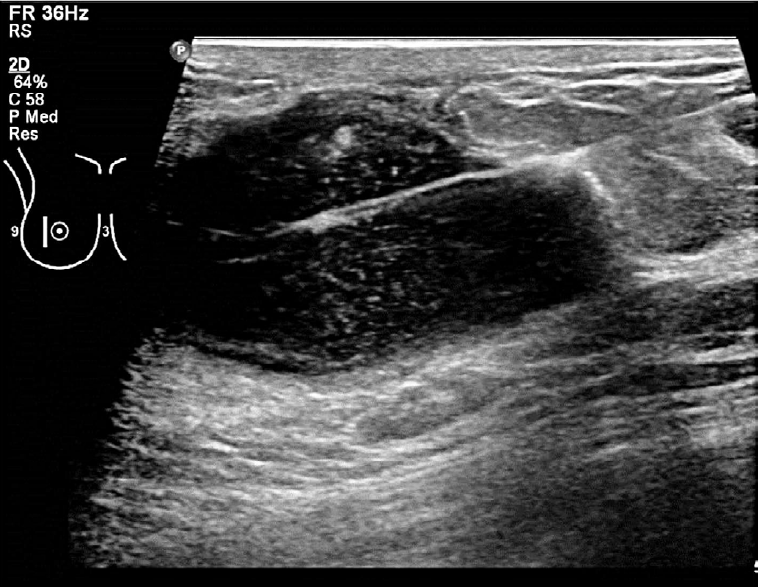

Ponctions et biopsies guidées par échographie

Pour un échantillonnage de qualité, 3 à 4 insertions de l’aiguille sont nécessaires dans le cas d’une biopsie. Celles-ci sont réalisées sous le contrôle permanent de l’échographe, pour confirmer la position de l’aiguille et éviter toute complication.